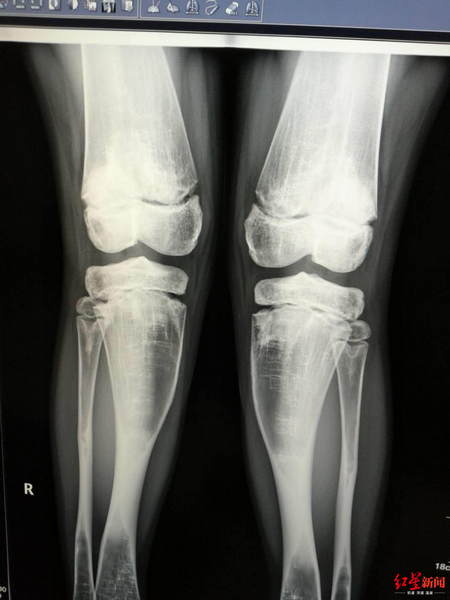

↑小女孩最终被确诊为患有石骨症,患者接受了DR检查。受访者供图

此时已经是7月1日,玄玄住进耳鼻咽喉头颈外科20多天,徐幼马上给玄玄安排了全身DR骨扫描检查,第二天出结果,徐幼第一时间到放射科看片子,结果让她大吃一惊,又反复去看了多次,脑海里蹦出一个词:石骨症。

原来,从片子上看,玄玄从头骨到四肢、到脊椎,全身的骨头都发生的变化,骨质密度增高,骨髓腔闭塞,“正常人,骨髓腔里都是红色的骨髓,有造血的功能,但她的骨头,已经石化改变。”徐幼说,简单地理解,玄玄的骨头,从中空的变成了实心的,像大理石一样。

石骨症,这是一种罕见的以骨密度增高、破骨细胞吸收功能障碍为主要特征的先天性遗传性骨发育障碍疾病,因表现为全身骨骼石样化改变,又被形象地称大理石骨病、广泛性脆性骨质硬化症、粉笔样骨。按照遗传方式,可分为常染色体显性或是隐形遗传,其中隐性遗传发病率为25万分之一。